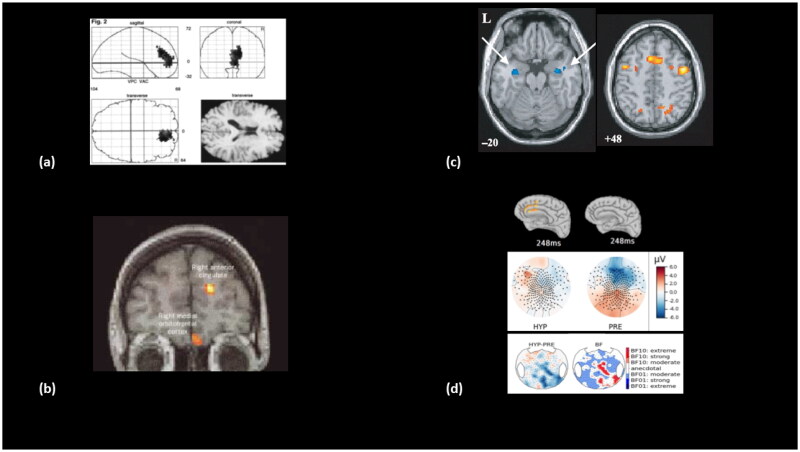

我们在此介绍一种基于以下假设的功能性神经障碍性疾病的一般模型:功能性神经障碍性疾病可能与有意识启动的自上而下的自愿过程相对应,该过程会导致非自愿的持久后果,而这些后果被患者有意识地体验和主观地解释为非自愿的。我们根据意识的全局神经元工作空间理论提出了这一核心假设,该理论特别适用于描述有意识和无意识认知过程之间的相互作用。然后,我们提出了一系列预测,并确定了一项研究计划,旨在对其有效性进行实证检验。最后,这一一般模型将引导我们重新解释长期争论不休的催眠暗示与功能性神经失调之间的联系。在科学和治疗目标的驱动下,这篇理论性论文旨在拉近功能性神经紊乱的精神和神经世界与意识认知神经科学最新发展的距离。

We introduce here a general model of Functional Neurological Disorders based on the following hypothesis: a Functional Neurological Disorder could correspond to a consciously initiated voluntary top-down process causing involuntary lasting consequences that are consciously experienced and subjectively interpreted by the patient as involuntary. We develop this central hypothesis according to Global Neuronal Workspace theory of consciousness, that is particularly suited to describe interactions between conscious and non-conscious cognitive processes. We then present a list of predictions defining a research program aimed at empirically testing their validity. Finally, this general model leads us to reinterpret the long-debated links between hypnotic suggestion and functional neurological disorders. Driven by both scientific and therapeutic goals, this theoretical paper aims at bringing closer the psychiatric and neurological worlds of functional neurological disorders with the latest developments of cognitive neuroscience of consciousness.